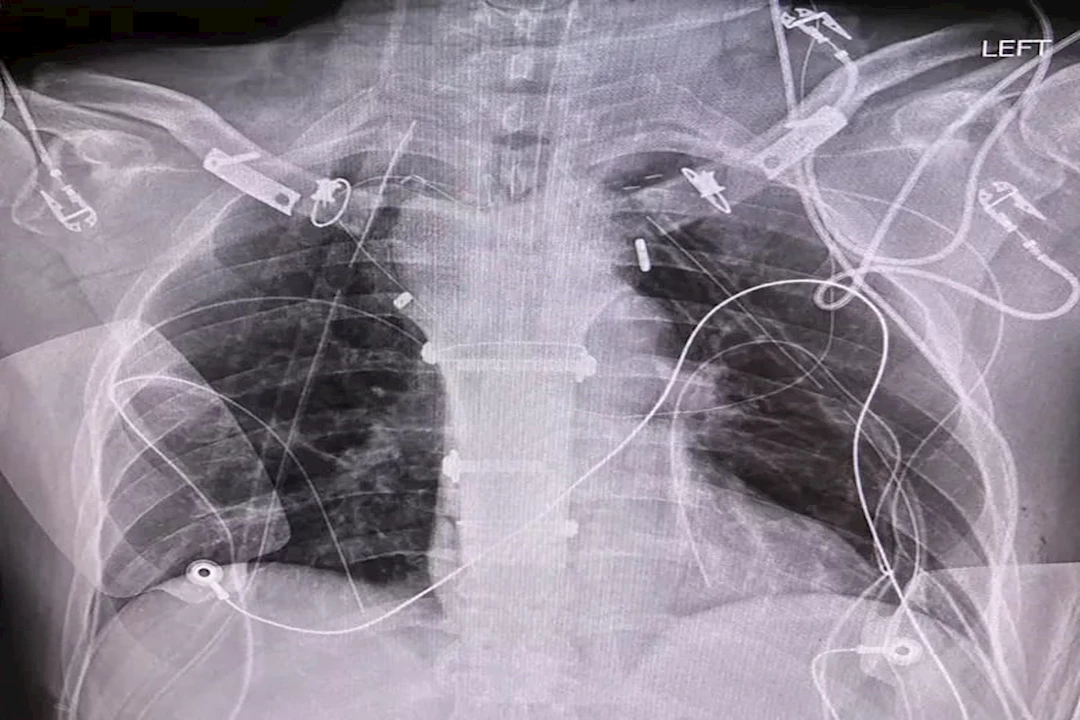

استئصال وإعادة بناء القفص الصدري

- خلال العملية، أزال جراح الصدر الورم وعظم القص، بينما قام جراح العظام بتشكيل الهيكل الجديد.

- ثُبّت عظم الفخذ المستخرج من الجثة بعظم القص المتبقي عبر مفصل شِعاري، مُثبّت بغرز جراحية.

- لبناء المفاصل القصية الترقوية، وُضعت أجهزة التثبيت "TightRope" أولًا لتثبيت عظم القص بعظمي الترقوة.

- لُفّ الطعم الأبهريّ، المُثبّت بعظم الفخذ بواسطة كابلات، حول النهايات المقطوعة لعظمي الترقوة،

- ثُبّت بكابلات إضافية.

- أخيرًا، نُسجت خيوط جراحية من البوليستر بين عظمي الترقوة بواسطة برغي مُقنّن في عظم الفخذ. غُطّي الهيكل بشبكة، مما يمنع انفتاق الرئة في العيوب الجانبية الصغيرة، ويوفر طبقة دعم إضافية.

بعد ثلاثة أشهر من الجراحة، أصبح المريض خاليًا من الألم وعاد إلى العمل، ونُصح بتجنب رفع الأشياء الثقيلة، وسيُتابع عن كثب ويُراقب عن كثب تحسُّبًا لانحراف العمود الفقري وأي تغيير قد يؤثر على بنيته، خاصةً بعد أن يتمكن من رفع ذراعيه بزاوية تزيد عن 90°، وسيُعزز النسيج الندبي من تثبيت بنيته.